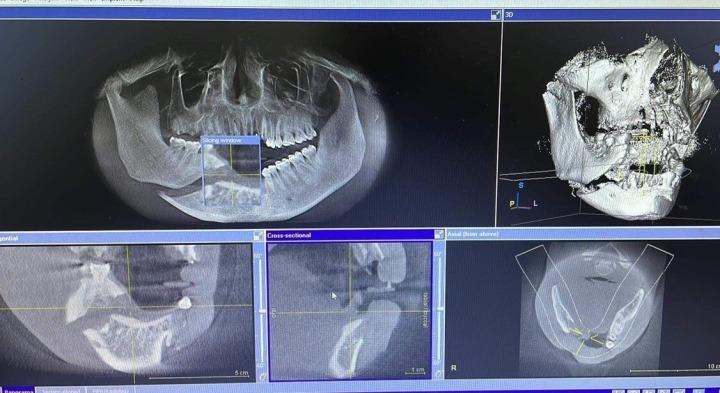

Hình ảnh chụp cho thấy nam bệnh nhân 32 tuổi mất toàn bộ răng cửa trên và dưới sau vụ tai nạn hi hữu. (Ảnh: BSCC)

Nam thanh niên 26 tuổi được đưa đến sơ cứu tại một cơ sở y tế trước khi đến Bệnh viện Hữu nghị Việt Nam - Cu Ba (Hà Nội). Bác sĩ Hoàng Phong Mỹ, Trưởng Khoa phẫu thuật hàm mặt, cho biết bệnh nhân được chẩn đoán vỡ nát xương hàm dưới phải, vỡ xương ổ răng hàm trên, dưới vùng cửa, mất toàn bộ răng cửa trên và dưới.

Bệnh nhân đã được phẫu thuật cấp cứu sau đó. Giữa tuần trước, bệnh nhân quay trở lại bệnh viện để trồng implant để có thể ăn nhai bình thường.